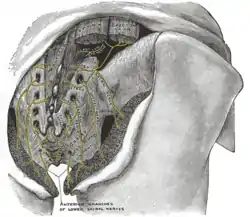

Sacrum, dorsal surface. (Multifidus attachment outlined in red.) | |

- in the sacral region: from the back of the sacrum, as low as the fourth sacral foramen, from the aponeurosis of origin of the sacrospinalis, from the medial surface of the posterior superior iliac spine, and from the posterior sacroiliac ligaments.

The posterior divisions of the sacral nerves.